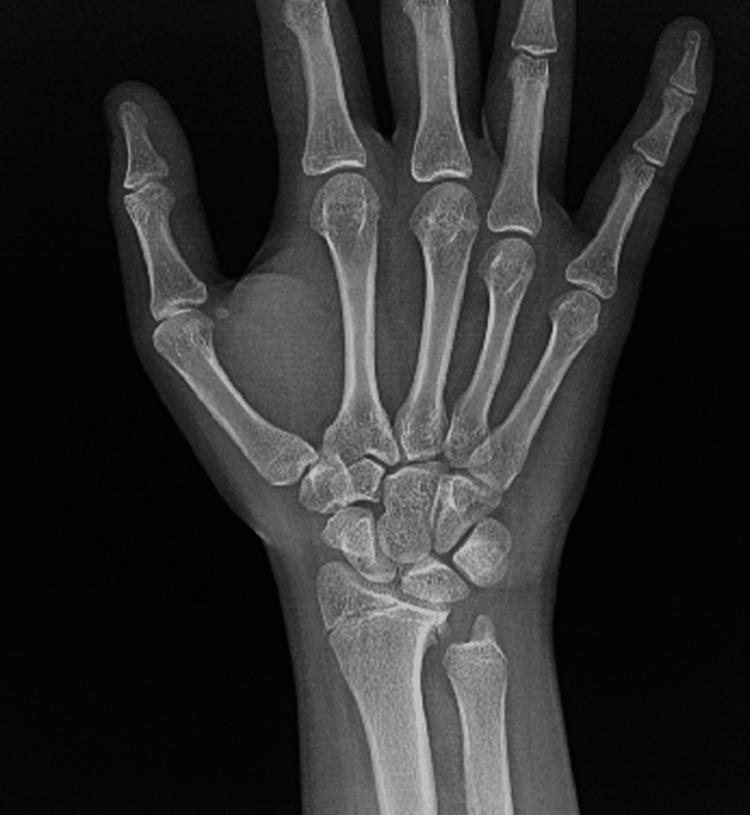

Fractures of the forearm are common among children and adolescents. Radial shaft fracture with dislocation of the distal radioulnar joint (DRUJ), called Galeazzi fracture, is unusual in pediatrics. The Galeazzi-equivalent fracture is a variant of the classic Galeazzi fracture that occurs in children and adolescents. It is a radius fracture associated with a distal ulnar displaced physeal injury without dislocation of the DRUJ. Our patient was a male, aged 15 years, who visited our emergency department after falling off a scooter onto his left hand. Left wrist X-rays showed a displaced Galeazzi-equivalent fracture. After a trial of close reduction, an X-ray showed a displaced and unstable fracture pattern. The patient was subsequently hospitalized for surgical intervention. Open reduction and internal fixation (ORIF) with a plate and screw were used for the radius fracture. The ulna fracture was irreducible; therefore, ORIF with two crossed smooth Kirschner wires (K-wires) was performed. Complete bone union was achieved, and he had a normal range of motion six months postoperatively. The patient is now able to perform daily and sports activities. At two-year follow-up, complications such as DRUJ instability or joint deformity did not occur. In conclusion, open reduction is desired for patients with malalignment or older patients who have a lower potential for sufficient bone remodeling. Regular serial follow-up sessions are required to assess growth arrest and the occurrence of other complications.

前臂骨折在儿童和青少年中很常见。桡骨干骨折合并下尺桡关节(DRUJ)脱位,即盖氏骨折,在儿科中并不常见。类盖氏骨折是经典盖氏骨折的一种变体,发生于儿童和青少年。它是一种桡骨骨折,伴有尺骨远端骨骺移位损伤,而DRUJ无脱位。我们的患者是一名15岁男性,骑滑板车时左手着地后前来我院急诊科就诊。左手腕X线片显示为移位的类盖氏骨折。试行闭合复位后,X线片显示骨折移位且不稳定。患者随后住院接受手术治疗。桡骨骨折采用钢板螺钉切开复位内固定(ORIF)。尺骨骨折无法复位;因此,采用两根交叉光滑克氏针(K针)进行ORIF。术后6个月实现了完全骨愈合,患者活动范围正常。患者现在能够进行日常和体育活动。在两年的随访中,未出现DRUJ不稳定或关节畸形等并发症。总之,对于骨折对位不良的患者或骨重塑潜力较低的年长患者,需要进行切开复位。需要定期进行系列随访,以评估生长停滞和其他并发症的发生情况。